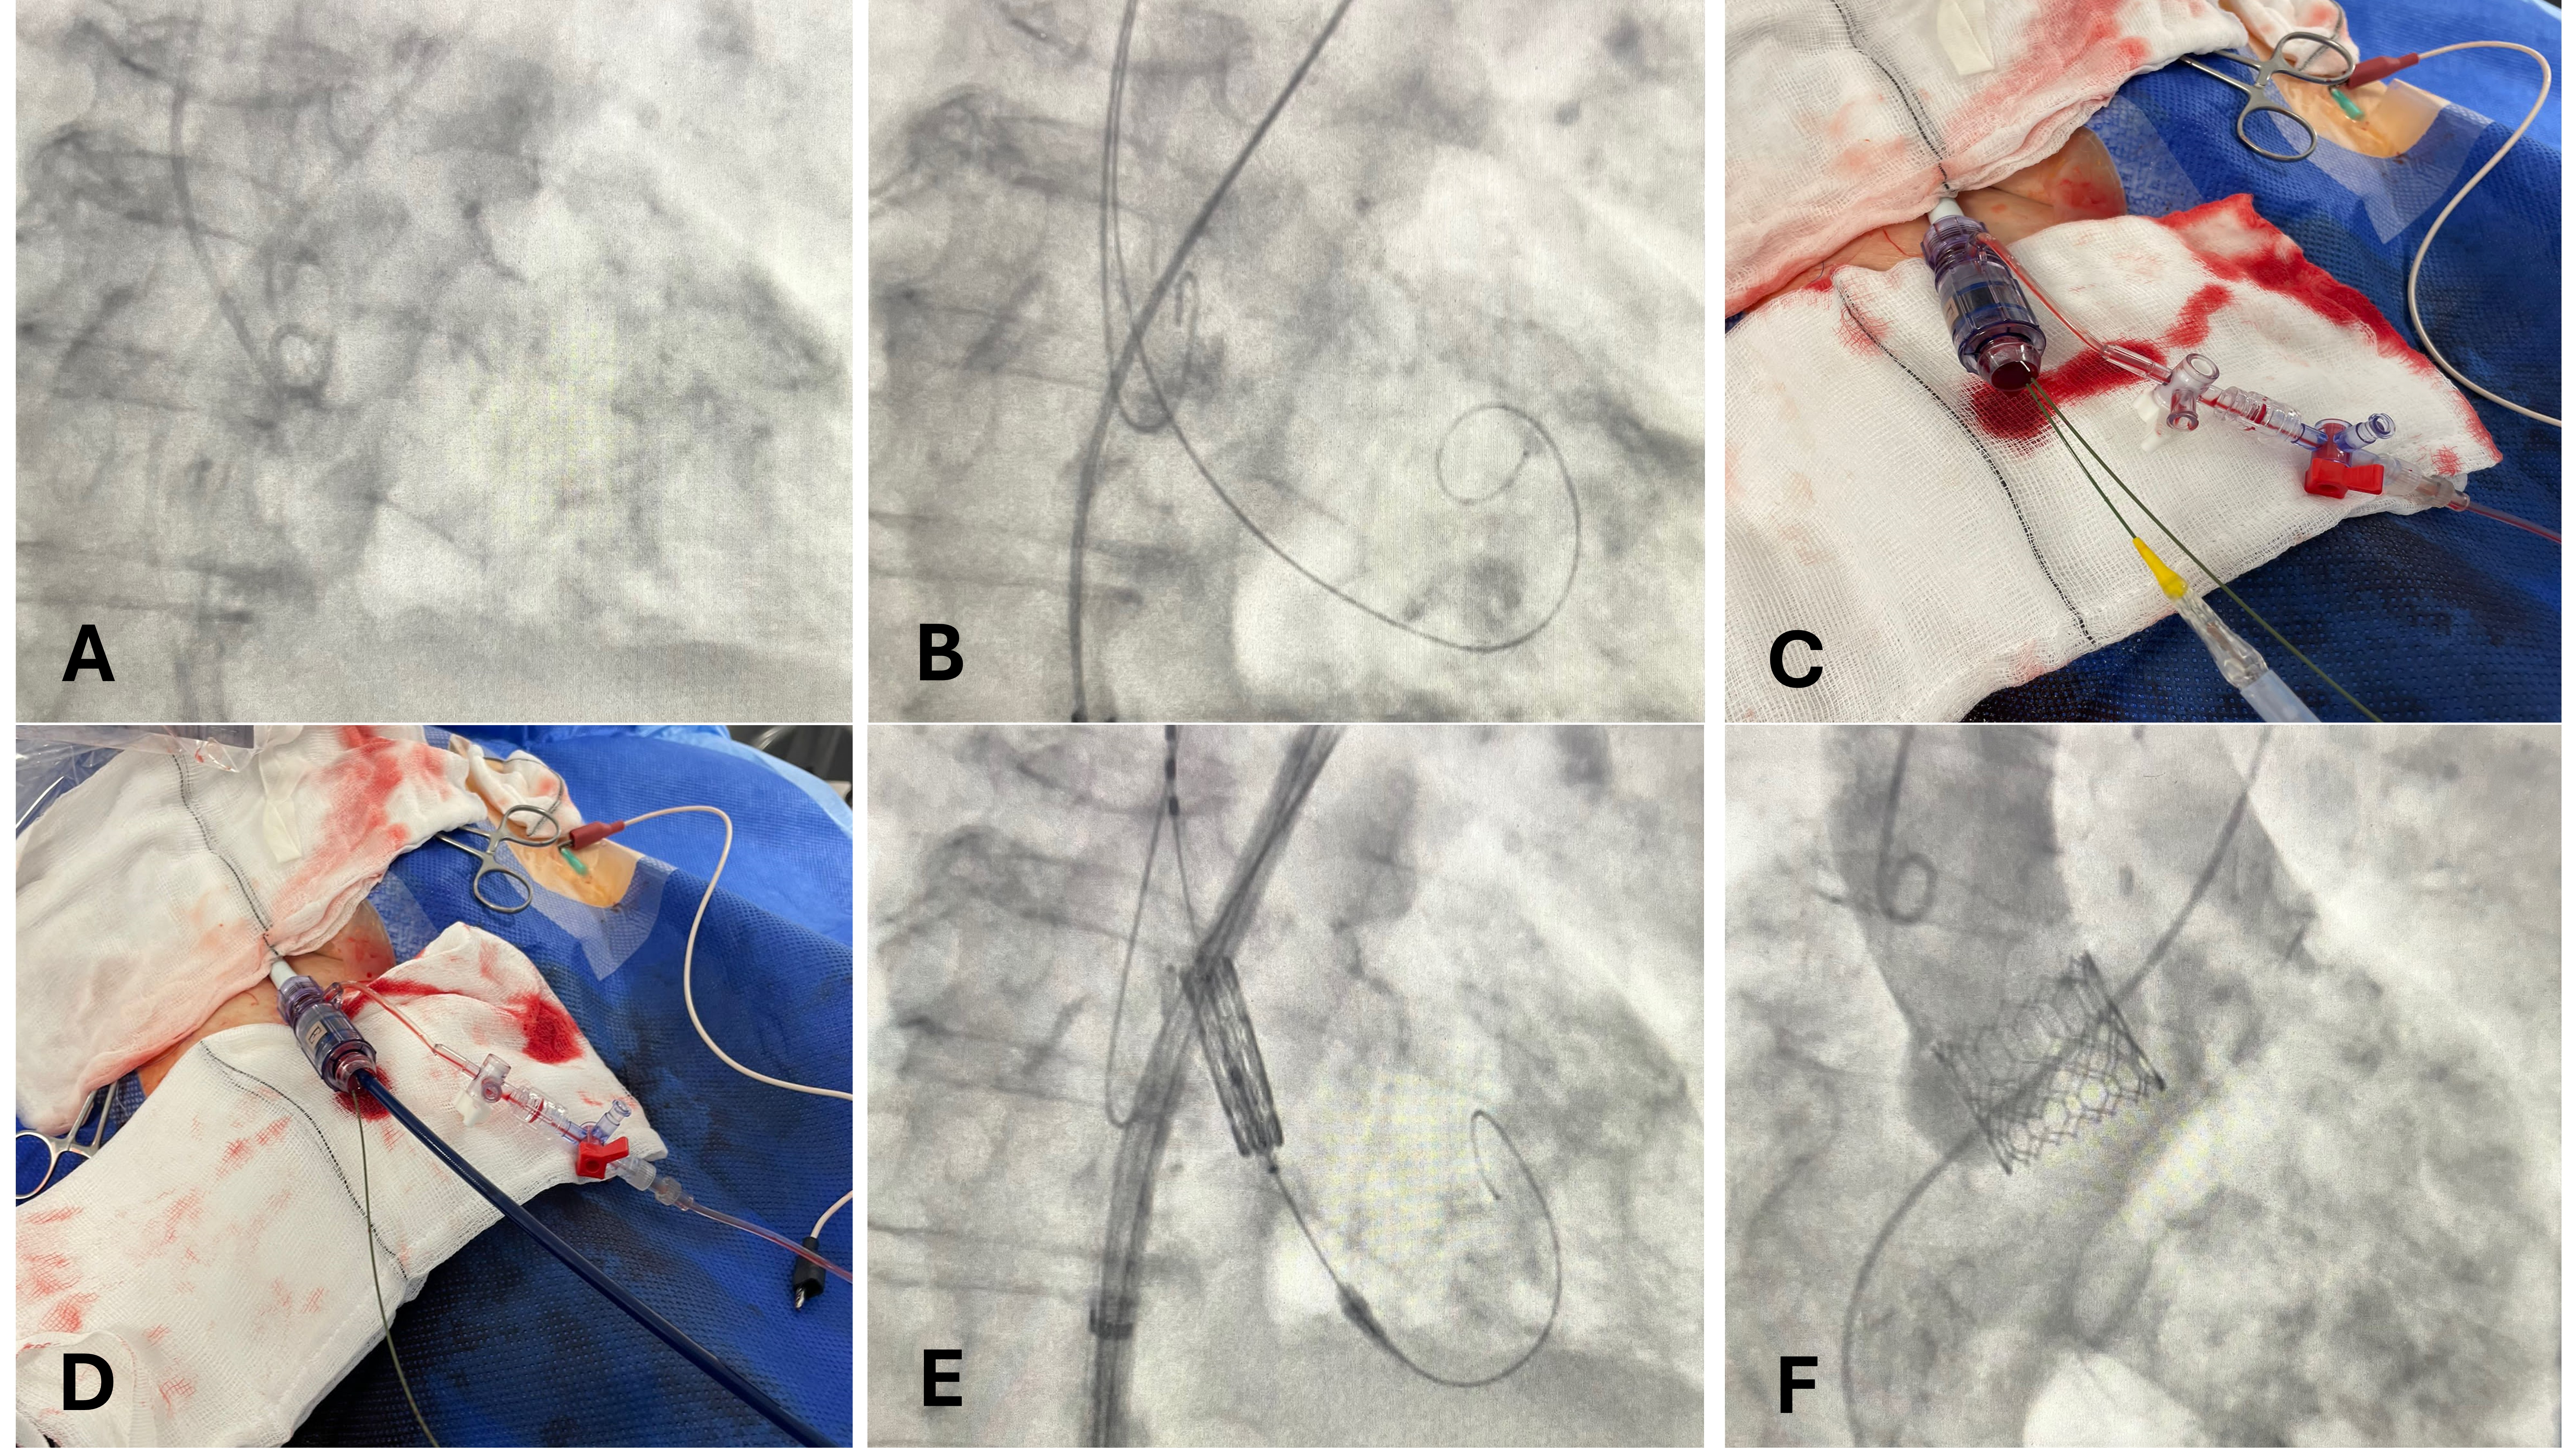

The procedure was planned as a single access TAVI using the right trans-femoral approach. A 16-French (Fr) eSheath (Edwards Lifesciences) was inserted and a 6-Fr pigtail was positioned in the noncoronary cusp (Figure A). The pigtail was exchanged over a standard 0.35-inch wire, which was left in the non-coronary cusp given the lack of calcification landmarks. A pre-shaped stiff wire was placed in the left ventricle in a standard fashion (Figure B).

A 29-mm Sapien Ultra THV (Edwards Lifesciences) was advanced into the eSheath with the parallel wire in place (Figure C, D). The THV was positioned at the annulus using the deflected portion of the 0.35-inch wire as a visual aid to match the bottom border of the balloon marker within the THV (Figure E). The THV was deployed under rapid pacing via the left ventricle wire and the position of the valve was confirmed using contrast under fluoroscopy (Figure F). The procedure was completed in a standard fashion without vascular complication or conduction disturbance. The patient made good clinical recovery and was discharged 2 days after the TAVI procedure.